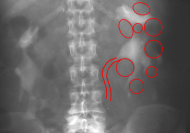

Die Diagnose wird mittels Anamnese (zystische Nierenerkrankungen in der Familie), RR-Messung, Labor (Kreatinin) mit genetischer Untersuchung, Sonographie, Computertomographie und gegebenfalls Kernspintomographie gestellt (Abbildung 4).

Ein i.v.-Pyelogramm kann im Rahmen der differentialdiagnostischen Abklärung des Flankenschmerzes indiziert sein (Abbildung). Sofern schon eine ausgeprägte Niereninsuffizienz vorliegt, sollte die Abklärung mit einem retrograden Pyelogramm erfolgen (Abbildung 5).